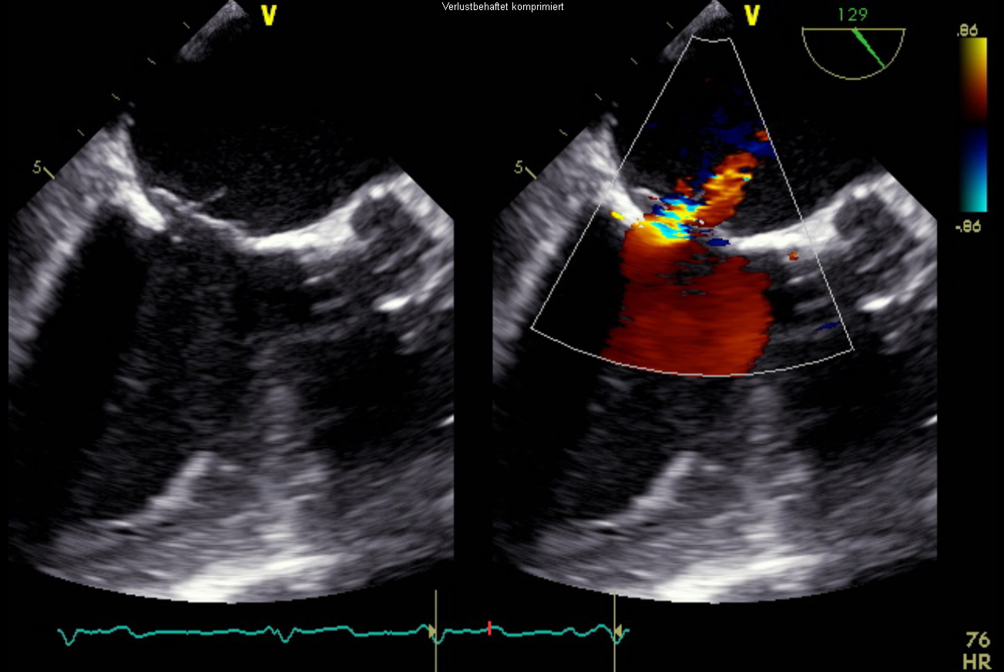

Nach Rückzug der transseptalen Schleuse kam es zu einem Anstieg des zentralen Venendrucks auf 20 mm Hg, einem Abfall des systolischen Blutdrucks auf 90 mm Hg sowie einem Abfall der Sauerstoffsättigung auf 80 %. In der transösophagealen Echokardiographie zeigte sich ein Atriumseptumdefekt mit einem relevanten Links-rechts-Shunt (Abb. 5). Es erfolgte der sofortige Verschluss mittels Vorhofseptumokkluder (GORE Septal Occluder 30 mm, Gore, Flagstaff, AZ, USA; Abb. 6). Hiernach zeigte sich kein Hinweis auf einen Restshunt auf Vorhofebene. Der zentrale Venendruck fiel auf 11 mm Hg, Blutdruck und Sauerstoffsättigung normalisierten sich.

Abb. 5

Transösophageale Echokardiographie. 2‑D-Ansicht in der kurzen Achse. Zu sehen ist der iatrogene Links-rechts-Shunt auf Vorhofebene

Bild vergrößern

Abb. 6

Transösophageale Echokardiographie. 2‑D-Ansicht in der kurzen Achse mit biplaner Darstellung. Zu sehen ist das implantierte GORE-Septal-Device (Gore) auf Vorhofebene